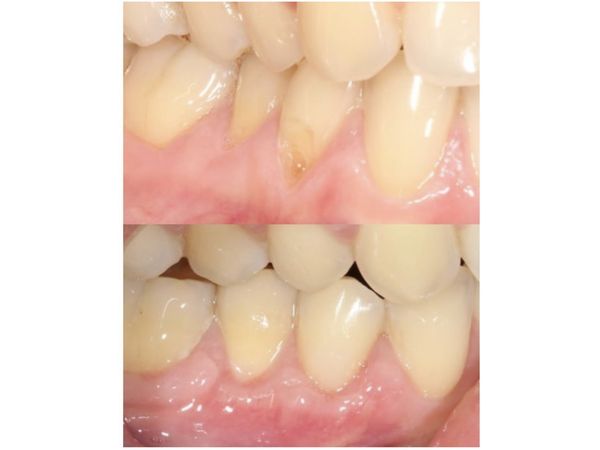

При осмотре полости рта на щёчной поверхности коронковой части зуба определялось клиновидное углубление, идущее по направлению к пульпе (нерву). Корень оголился на 3 мм. Слизистая оболочка, окружающая зубы 4.4 и 4.5, покраснела и отекла. Десна кровоточила при зондировании. Воздействие температурных раздражителей сопровождалось резкой болью.

Рана заживала без особенностей. Швы сняли через 2 недели. Спустя ещё неделю удалось оценить результат лечения: рецессия десны была полностью закрыта.